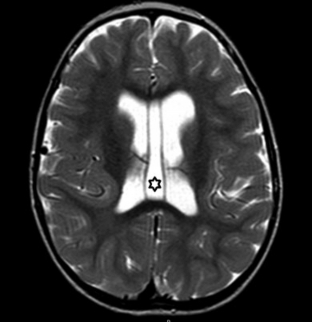

Constituyen variantes anatómicas que se presentan en la línea media derivando de alteraciones del desarrollo del septum pellucidum (SP).7 En TC y RM se los aprecia con densidad o señal similar al LCR (►Figs. 1, 2, 3).7

RM de cerebro corte axial ponderada en T2: se evidencia una cavidad interpuesta entre los ventrículos laterales (asterisco). Corresponde a cavum vergae (CV) asociado a CSP.